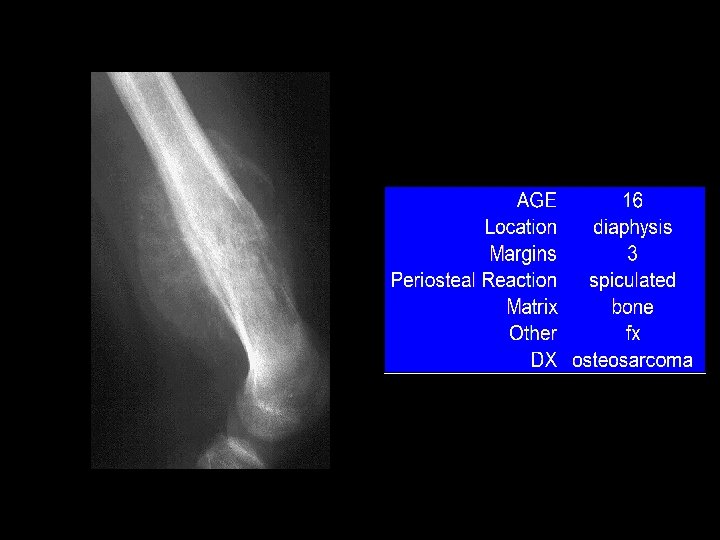

A 14 year old boy presents with pain and a mass above the knee. Take a look at the AP and lateral radiographs first.

In case of Bone Tumors: look for Location! Age Age Behavior

Location and age of patient most important • parameters in classifying a primary bone tumor. Simple to determine from plain • radiographs.

Reaction of bone to tumor Limited responses of bone • destruction: lysis (lucency) reaction: sclerosis remodeling: periosteal reaction Rate of growth determines bone • response slow progression, sclerosis prevails – rapid progression, destruction prevails –